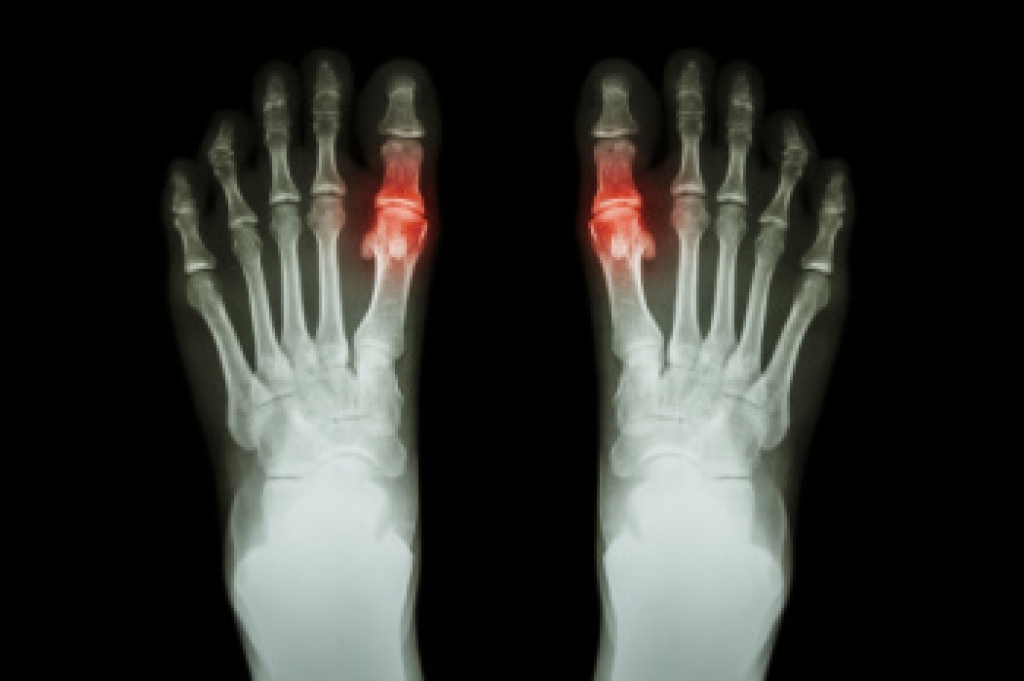

How Podiatrists Can Test for Gout

Gout is a type of arthritis that occurs when there is a buildup of uric acid in the body, leading to the formation of sharp crystals in the joints. This often results in sudden, severe pain and swelling, particularly in the big toe. When testing for gout, a podiatrist typically starts by reviewing a patient’s symptoms and history. To confirm a diagnosis, lab tests may be used, such as checking uric acid levels in the blood. A higher level of uric acid can indicate gout, but it is not always conclusive. Joint fluid analysis is a more definitive test, where fluid is taken from the affected joint and examined for uric acid crystals. Imaging tests like ultrasounds or X-rays may also be performed to detect urate crystals or rule out other conditions causing the joint pain. A podiatrist then monitors uric acid levels during treatment to ensure it is effective and adjusts the plan as needed. If you are experiencing big toe pain that may be caused by gout, it is suggested that you schedule an appointment with a podiatrist.